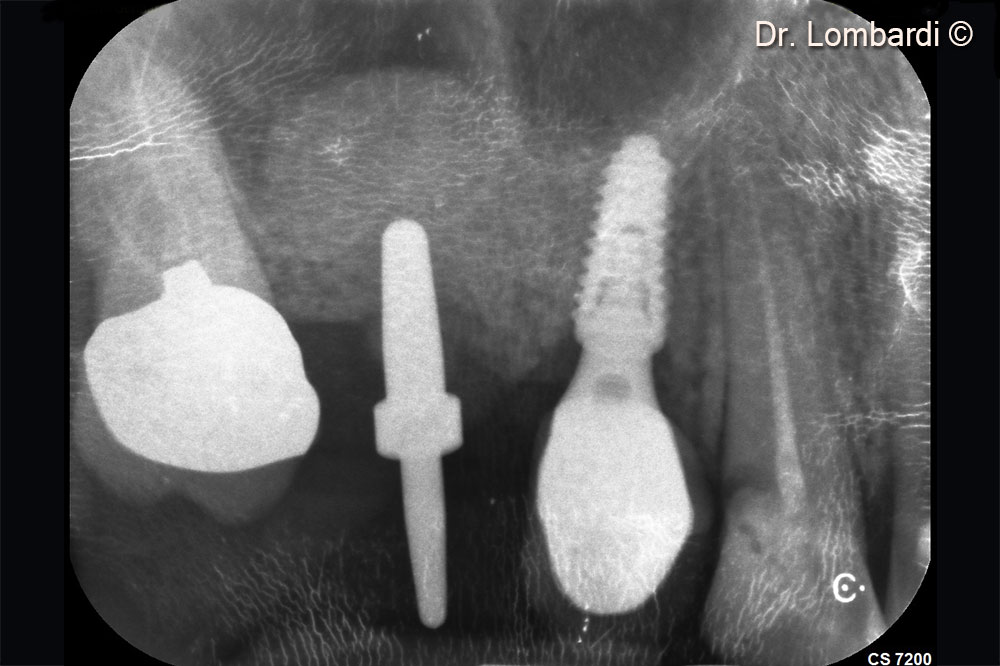

Immediate implant insertion is required to counteract the physiological biomaterial shrinkage